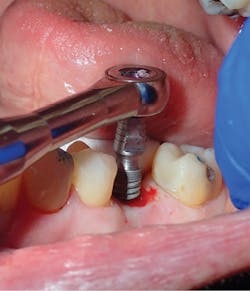

Being a network of small- to medium-sized private practice groups, we negotiated volume pricing on our favorite suite of manufacturer-direct systems. It is these systems that were uncovered during this process that we will highlight in the clinical portions of this series. We secured high-volume, manufacturer-direct, DSO-like pricing, and we call ourselves the Implant Alliance.In our practice of four dentists in Allen, Texas, we have been very intentional about making sure we can deliver incredibly high-quality dentistry at affordable rates for our patients. The case shown this month (figures 7–12; courtesy of Mike Dostal, DDS, FICOI) represents a very typical “I just need my tooth replaced” kind of day in our office. You see a patient in hygiene who has been missing a tooth for years and just didn’t want a bridge. Now, we can offer a simple appointment to place a flapless, sutureless implant, and the patient probably can go right back to work the same day.

The implant systems that satisfy this challenge the best for us are the iHex 1, 2, and 3 and MorsTorq systems by iH Biomedical. The iHex series is an internal hex that is compatible with most of the major internal hex systems. It incorporates platform switching, which allows for crestal or subcrestal placement. The designers created a multicompatibility surgical kit that minimizes the number of drills (often just one needed) used to place and restore the implants. The platforms are the same across most sizes, which reduces the number of abutments that must be stocked. Also, the implant, abutment, and cover screw are all included. These design features place this system at the top of the list when it comes to economics and excellence rolled into one package.